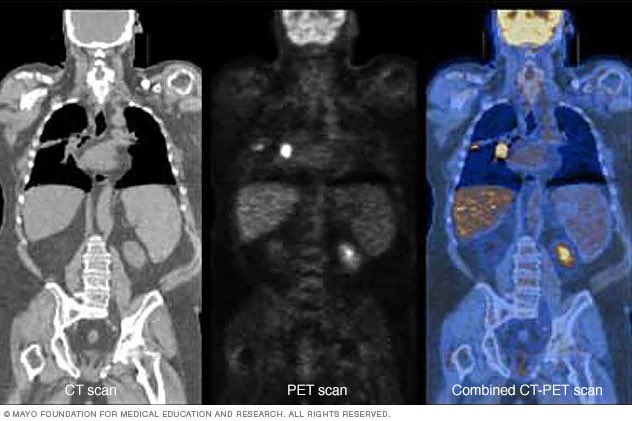

(PET scan ) التصوير المقطعي باالاصدار البزيترني ويعتير من احدث التطورات في المجال ويساعد بفحص النشاط الكيميائي بالجسم ويساهم باكتشاف الامراض في مراحلها الاولى والتي لاتظهر في اجهزة الاشعة مثل السرطانات وانتشارها وامراض القلب والدماغ .